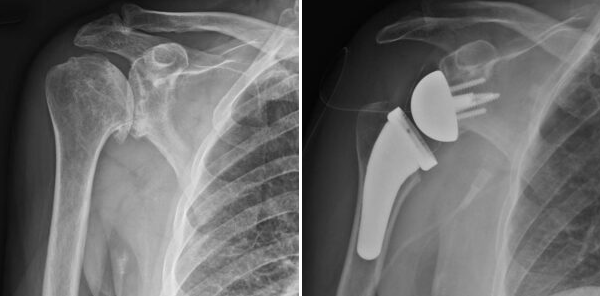

X-rays showing advanced arthritis of shoulder and postoperative picture after a reverse shoulder replacement.

Reverse shoulder replacement reconfigures the shoulder’s anatomy to use the deltoid muscle for arm movement instead of the rotator cuff. This is achieved by placing a ball component on the shoulder blade (glenoid) and a socket component on the upper arm bone (humerus), effectively reversing the natural ball-and-socket joint.